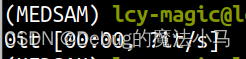

这回就好了: